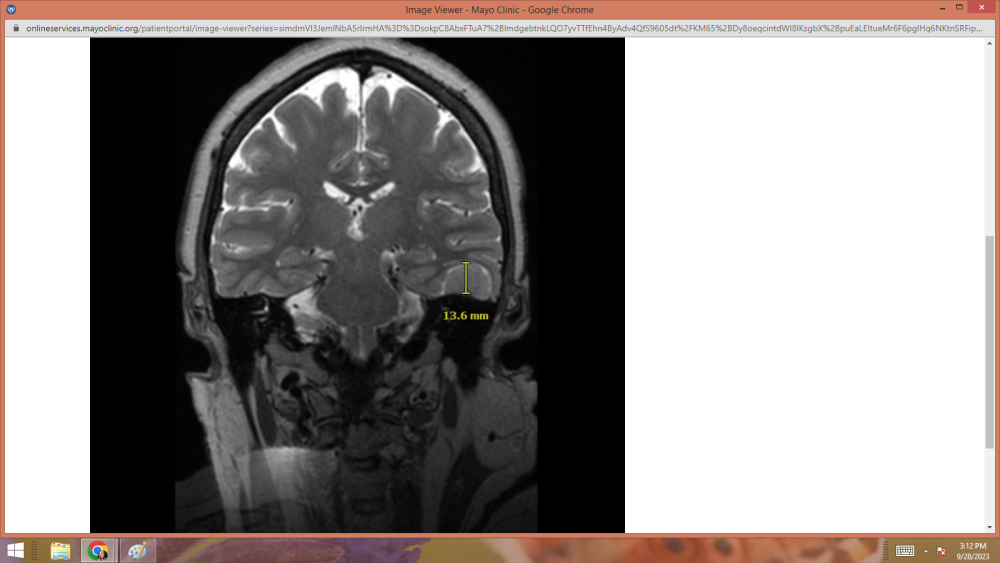

UPDATE:     GOOD NEWS!!!   My tumor hasn't grown any since 2019.

Thank you brothers and sisters for the prayers.    They were felt.

scan1.png

scan2.png

scan3.png

scan4.png